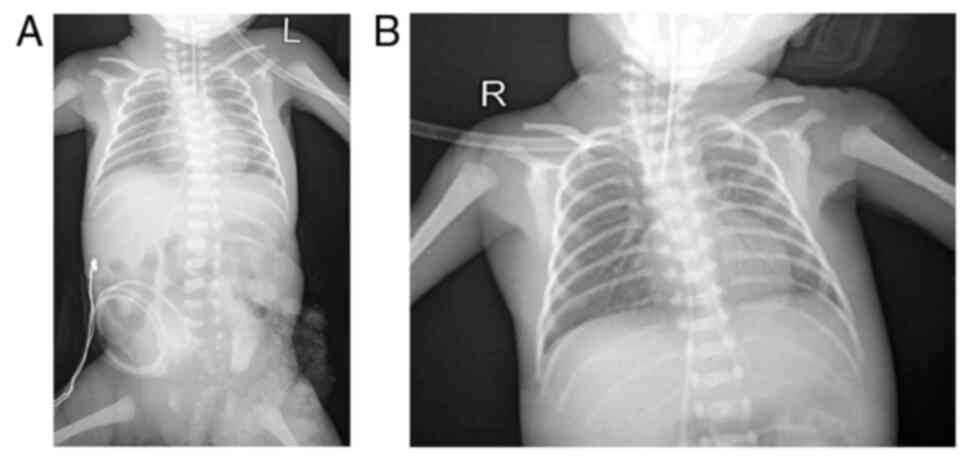

Thoraco-abdominal radiography was also performed in the patient in the present study (Fig. 3), and this indicated grade IV hyaline membrane disease with grade II NEC. An echocardiogram revealed a patent foramen ovale with good heart contractility. Haematological analysis revealed haemoglobin levels of 15.5 g/dl, a haematocrit of 44.1%, a leukocyte count of 5.75x103/µl, and blood type O positive.

Figure 3

Radiological improvement in the chest X-ray of the patient pre- and post-surfactant administration. (A) Initial chest X-ray shortly after birth, prior to surfactant administration, illustrating low lung volumes and air bronchograms indicative of hyaline membrane disease. (B) Subsequent chest X-ray, at 11-12 h post-surfactant administration (4 ml/kg BW followed by 3 ml/kg BW), illustrating enhanced lung expansion, improved aeration and reduced lung opacities. BW, body weight.